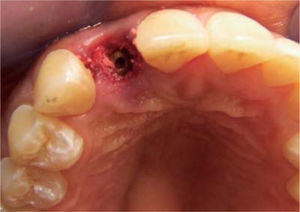

Anestesia local infiltrativa (lidocaína clorhidrato al 2% roxicaína) fue aplicada en la zona del incisivo lateral superior derecho, después de esto la exodoncia preservando el alvéolo (Figura 3). Se coloca un implante Replace Select (Nobel Biocare) de 3.5 x 13 mm. La estabilidad primaria del implante fue confirmada mediante la inserción de torque a 35 Ncm; para compensar las alteraciones de la pared vestibular, el espacio entre el implante y la pared bucal fue sellada con injerto óseo Bi-Oss de partícula pequeña medular (Geistlich Pharma) (Figura 4). A continuación fue provisionalizado de manera inmediata con un pilar plástico prefabricado (Nobel Biocare) (Figura 5).